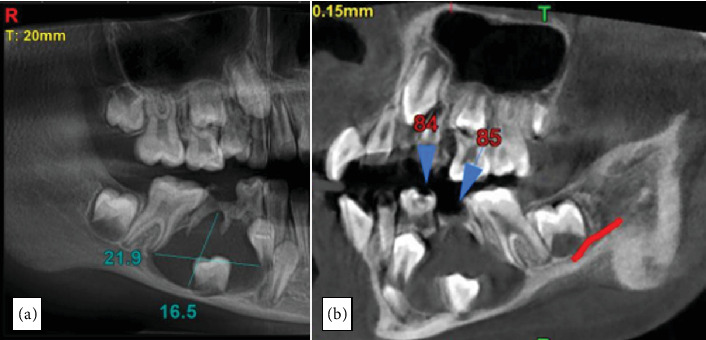

牙源性囊肿(dc)是一种牙源性囊肿,通常与未出牙或阻生牙的牙冠有关,通常在牙长得很大或感染时发现。虽然在成人中很常见,但在儿童中很少发生。大多数儿童病例是在常规乳牙感染x线检查中偶然发现的。治疗方法因病变的大小和范围而异,剜出和有袋化是常用的方法。尽管技术不同,总体预后和治疗结果通常是有利的。本病例报告描述了一名8岁女性通过有袋化结合定制丙烯酸闭孔成功保守治疗下颌骨DC。

Dentigerous cysts (DCs) are odontogenic cysts typically associated with the crowns of unerupted or impacted teeth and are usually discovered when they reach large sizes or get infected. Although common in adults, their occurrence in children are rare. Most cases in children are incidentally discovered on routine radiographic examination of infected deciduous molars. Treatment methods vary based on the size and extend of the lesion, with enucleation and marsupialization being the commonly employed approaches. Despite the variation in techniques, the overall prognosis and treatment outcomes are generally favorable. This case report describes the successful conservative management of a mandibular DC in an 8-year-old female through marsupialization in conjunction with a custom-made acrylic obturator.